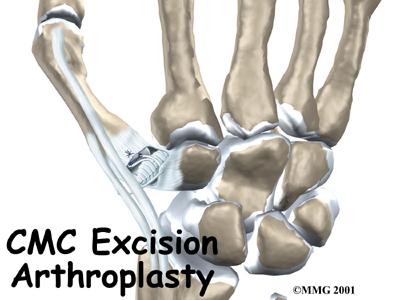

Resection (Excision) Arthroplasty of the Thumb

Thumb arthritis may be surgically treated with a procedure called resection arthroplasty or sometimes called excision arthroplasty. The term excision means to take out. In this surgery, the surgeon takes out a small bone at the base of the thumb and fills in the space with a rolled up section of tendon. The soft tissue forms a false joint that keeps the thumb somewhat mobile and stops pain by preventing the joint surfaces from rubbing together.

Excision Arthroplasty of the Thumb

Thumb arthritis may be surgically treated with a procedure called excision arthroplasty. The term excision means to take out. In this surgery, the surgeon takes out a small bone at the base of the thumb and fills in the space with a rolled up section of tendon. The soft tissue forms a false joint that keeps the thumb somewhat mobile and stops pain by preventing the joint surfaces from rubbing together.